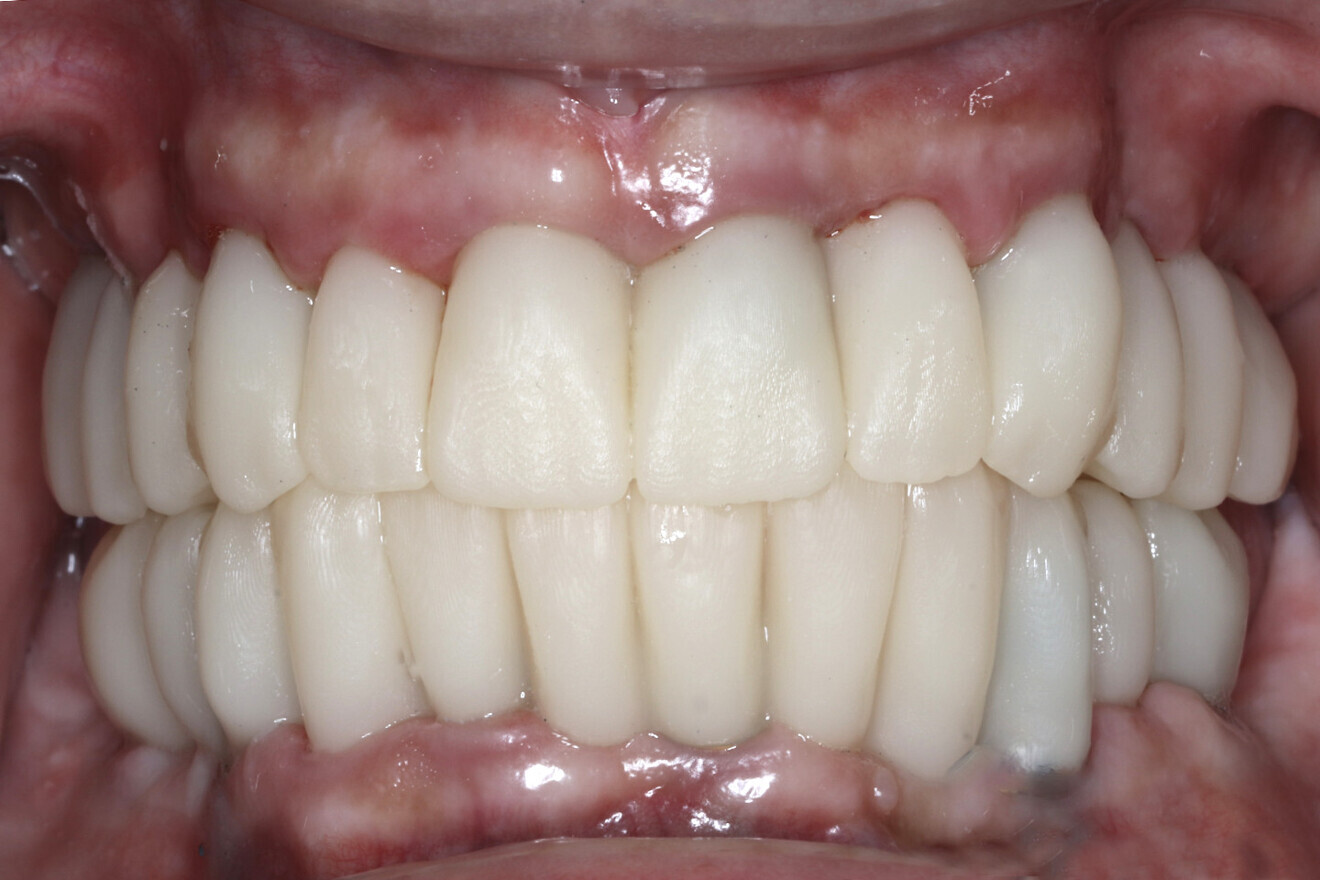

Fig. 16b: Retracted intra-oral view.

Fig. 17b: Retracted intra-oral view.

The data collected was sent through a scanning software portal (Medit Scan for Clinics) to the dental laboratory with requested changes for correction of the desired smile design. Utilising advanced planning features in the design software (exocad), the midline and tooth size changes were corrected. 3D-printed maxillary and mandibular PMMA restorations were used for try-in using the direct-to-MUA screws (Vortex LA VIS; Fig. 16a). Fit, phonetics, aesthetics and occlusion were evaluated and confirmed using digital articulation (OccluSense; Fig. 16b). The patient was extremely satisfied with the printed try-ins. Since no adjustments were required, the patient was allowed to leave with the printed try-ins as new provisional restorations made from extra-strong resin. The new provisional restorations were worn for ten days to confirm form and function. The final shade was chosen, and metal-free monolithic zirconia restorations were then fabricated by the laboratory.

The final restorations were passively and accurately seated ten days later uneventfully using Vortex LA VIS screws. Confirmation records were taken with photographs, radiographs and digital articulation to recheck fit, function, phonetics and occlusion (Fig. 17a). The patient was extremely satisfied with his final restorations, describing the process as life-changing and surprisingly fast in comparison with what he had heard about full-mouth implant therapy. He was especially pleased with the speed at which the final process was able to be completed (Figs. 17b & c).